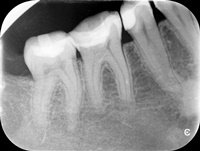

Nieczęsty przypadek trzykanałowej dolnej piątki, przed i po reendo.

Przed i po reendo.